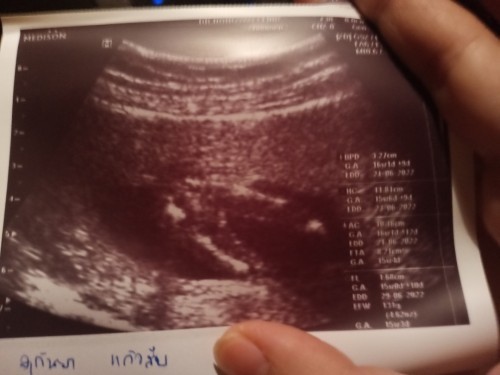

ยังงี้มองออกไหมคะ ว่าเพศอะไร

ช่วยดูหน่อยคะแม้ว่า บ้านนี้หญิงหรือชาย

เห็นชัดเลยค่ะ ผู้ชายแน่นอนค่ะแม่

ชายล้าน%ของบ้านนี้เหมือนแม่เลยคะ

ไอ้จู๋100%ค่ะคุณเเม่. ไข่ชัดเเจ๋ว